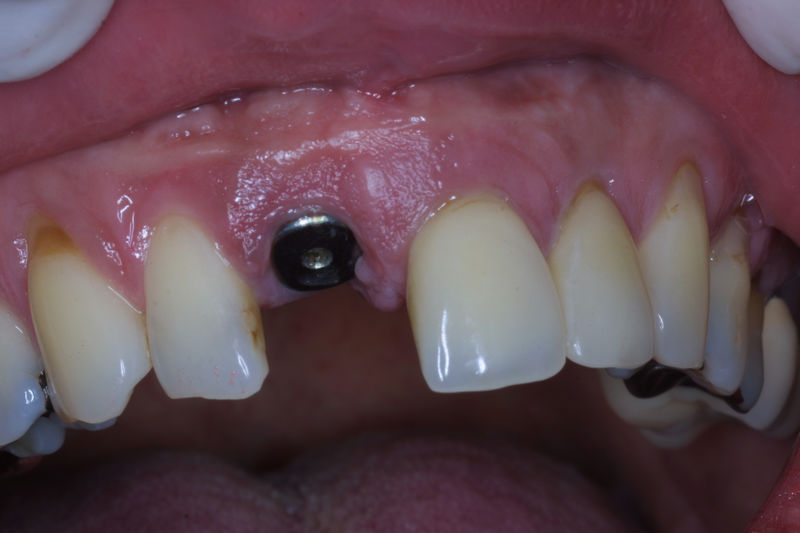

Los implantes dentales son pequeños tornillos de titanio u otro material biocompatible que se insertan en el hueso maxilar o mandibular para sustituir la raíz de un diente perdido. Actuando como un soporte sólido sobre el cual el dentista puede colocar un diente artificial (corona), un puente o una prótesis completa.

Son estructuras de titanio las cuales se colocan en el hueso y se utilizan para soportar coronas, prótesis fijas, removibles y totales. La colocación de los implantes se hacen previo análisis tomográfico.

Implante fracasado, extracción, carillas, coronas y prótesis fija.